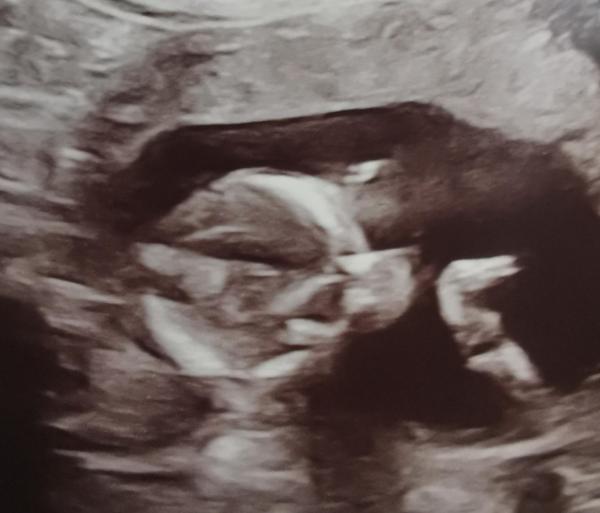

Huhu. 🤗 Ich hatte heute den nächsten Ultraschall und den ersten Zuckertest.  Die Auswertung des Präeklampsie Screenings war auch dabei, ich habe kein erhöhtes Risiko. 🥳 Das erleichtert uns sehr, da die Einnahme von ASS für mich schwierig bis ausgeschlossen gewesen wäre. Vom Zuckertest gibt's bereits morgen den Anruf, ob alles in Ordnung war. Ich bin gespannt. Beim Ultraschall zeigte sich wieder, dass unser Mäuschen immer noch schneller wächst als es muss. Sie wiegt jetzt schon 140g.  Sollte der Zuckertest (vorerst) in Ordnung sein, dann liegt es wohl einfach daran, dass sowohl mein Mann als auch ich große Menschen sind. Ansonsten haben wir noch den Kopfumfang genannt bekommen, das sind schon 13cm, und der Oberschenkelknochen ist bereits 2cm lang. Wie groß sie insgesamt schon ist, hat sie nicht gemessen. Ich vermute, es lag an der Aktivität unserer Maus.  Meine Ärztin bestätigte die Vorderwandplazenta, meinte aber auch gleichzeitig, dass das was ich spüre durchaus schon die Kindsbewegungen sein können. Die Plazenta nimmt ja noch nicht die gesamte Vorderwand der Gebärmutter ein und unsere Maus ist sehr aktiv. Hat man heute auch wieder auf dem Ultraschall deutlich gesehen. Sie wackelte und zappelte hin und her, ist sogar ein kleines bisschen gehüpft. Einmal sah es sogar so aus, als würde sie in die Hände klatschen. Total süß und sie hatte auch die ganze Zeit die Hände immer wieder am Kopf und Gesicht. Die Ultraschall-Bestätigung, dass wir ein Mädchen bekommen, haben wir auch bekommen. 🩷 Es war sehr deutlich zu sehen, der NIPT-Test hat also die Wahrheit gesprochen. 😁 In meinem Bauch hat sich unabhängig von dem Mäuschen viel getan, das hatte ich ja aber schon gemerkt. Meine Rektusdiastase ist bereits sehr breit, alles schon weit nach oben gewandert. Der Fundusstand liegt bereits einen Querfinger unter dem Nabel, das erklärt, wieso mein Bauch schon so unübersehbar ist. Normalerweise wäre das erst zwischen Woche 20-24 zu erwarten, aber es ist ja auch nicht meine erste Schwangerschaft. Das erklärt aber leider auch, wieso ich schon Ischiasbeschwerden habe. Mir wurde jetzt empfohlen, es mit Tapen zu probieren. Den nächsten Vorsorge-Termin habe ich dann in der Woche vor Weihnachten, da ist dann das 2. große Screening, da bin ich dann in der 19. Woche. Wie geht es euch? Was gibt es Neues? Viele Grüße Susuba, 15+1